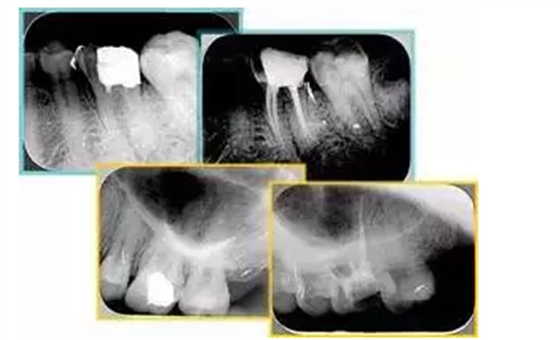

共有 4 張 X 線片,分別是術(shù)前、診斷絲 、主牙膠尖確認(rèn)、術(shù)后。

( 1 )術(shù)前:術(shù)前 X 線片用來了解牙齒的大概情況。術(shù)前預(yù)期為多根牙時(shí) X 線片應(yīng)偏頭拍攝。

( 2 )診斷絲:根據(jù)術(shù)前 X 線片進(jìn)行開髓、根管的初步預(yù)備后,需要插入診斷絲,用來指示工作器械位置。常用 10 號(hào)或 15 號(hào)擴(kuò)大器作為診斷絲插入牙髓腔。

( 3 )主牙膠尖確認(rèn):通過術(shù)前預(yù)期和診斷絲診斷,明確工作長(zhǎng)度、牙根走向,進(jìn)行根管預(yù)備。之后應(yīng)進(jìn)行主牙膠尖(中銼)確認(rèn),已明確根管是否適合充填。

( 4 )術(shù)后:觀察治療效果。

左圖為根管充填術(shù)后 X 線片。圖中可見,根管充填較好。右下圖有白色小點(diǎn),為側(cè)方加壓導(dǎo)致糊劑擠出所致,表明根管充填比較致密。

致密、恰到好處的充填可去除干凈根管里感染灶,機(jī)體逐漸恢復(fù)。

多根牙時(shí)候需進(jìn)行偏移投照,正位投照無法說明具體哪根牙根管充填效果。 二、根管預(yù)備及充填要求